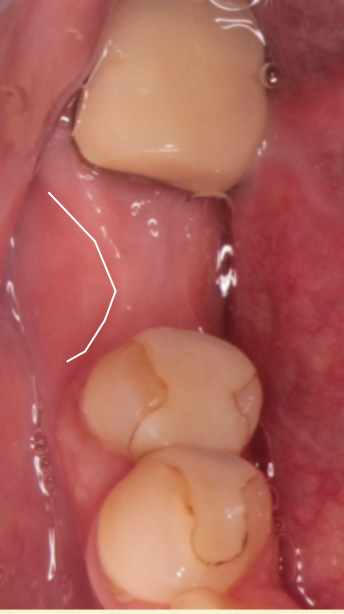

抜歯した部位の歯肉及び骨が再生した状態です。写真の白い線のように歯茎が少しえぐれた感じで治ることが多いです。この「えぐれ」が大きい場合には太いサイズのインプラントが入らないのでオプションで骨造成術を併用する場合があります。